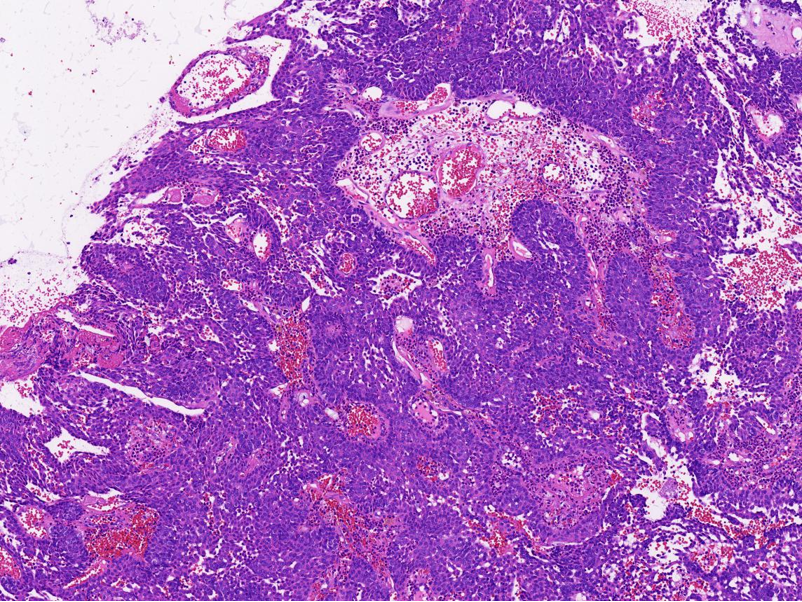

第一次手术送检:灰白碎组织一堆,合计直径1.4cm,切面灰红,质地较脆。

第二次手术送检:暗红色不整形肿块一堆,大小合计2.0cm×1.5cm×0.7cm,切面灰红,质地较脆。另送泪囊周围暗红碎组织一堆,合计直径0.5cm,质地较脆。

病理特征:宽薄乳头、 迷宫样内翻生长、单一肿瘤细胞形态、棘层松解、显著中性粒细胞浸润;

可见:细胞旋涡、透明细胞变、微囊形成、黏液纤毛上皮帽、部分肿瘤细胞异型性增加、坏死。